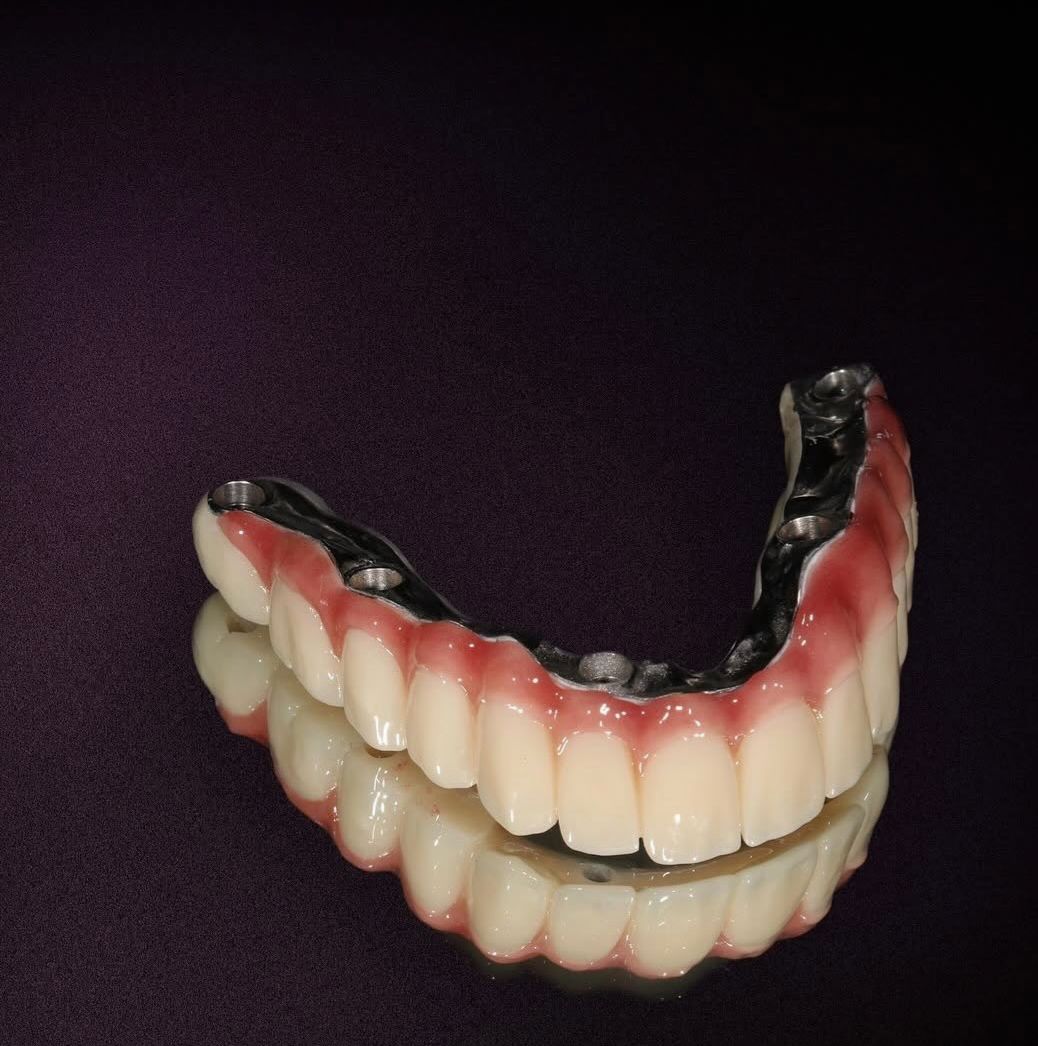

İmplant tedavisi

İmplant Tedavisi ile Kalıcı ve Güvenli Çözüm

İmplant tedavisi, eksik dişlerin yerine çene kemiğine yerleştirilen titanyum vidalar sayesinde doğal diş fonksiyonunu yeniden kazandıran modern ve kalıcı bir yöntemdir. Kemikle biyolojik uyum sağlayan implantlar, üzerine yerleştirilen protezlerle birlikte hem estetik hem de fonksiyonel açıdan güçlü bir sonuç sunar.

Eksik dişler zamanla kemik kaybına ve çevre dişlerde bozulmaya neden olabilir. İmplant tedavisi, kemik yapısını destekleyerek bu sürecin önüne geçmeye yardımcı olur. Sağlam bir temel, sağlıklı ve özgüvenli bir gülüş demektir.

İmplant Tedavileri

• Dental implant uygulamaları

• İmplant üstü sabit protezler

• İmplant üstü hareketli protezler

• All-on-4 ve All-on-6 tedavi sistemleri